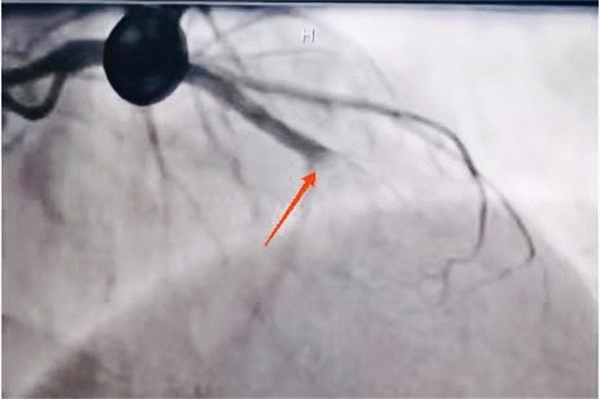

王先生的冠脉造影结果让在场医务人员捏了一把冷汗:前降支中段以远完全闭塞,可见明显的血栓影。“正常人心脏上冠状动脉主要有三根血管,分别是前降支、回旋支和右冠状动脉,其中任何一支血管堵塞都非常严重。患者前降支血管堵塞,风险可想而知,随时会面临猝死的危险!”综合分析判断后,心内科专业团队在副主任彭宇的带领下决定疏通罪犯血管—前降支。

PCI术前造影